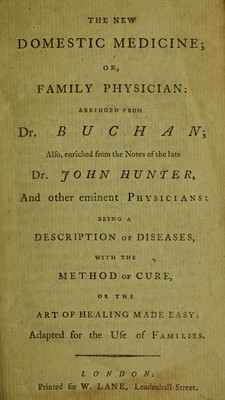

The new domestic medicine ... / abridged from Dr. Buchan; also ... the notes of J. Hunter, and other eminent physicians.

- William Buchan

- Date:

- [between 1790 and 1799?]

Licence: Public Domain Mark

Credit: The new domestic medicine ... / abridged from Dr. Buchan; also ... the notes of J. Hunter, and other eminent physicians. Source: Wellcome Collection.

1/296